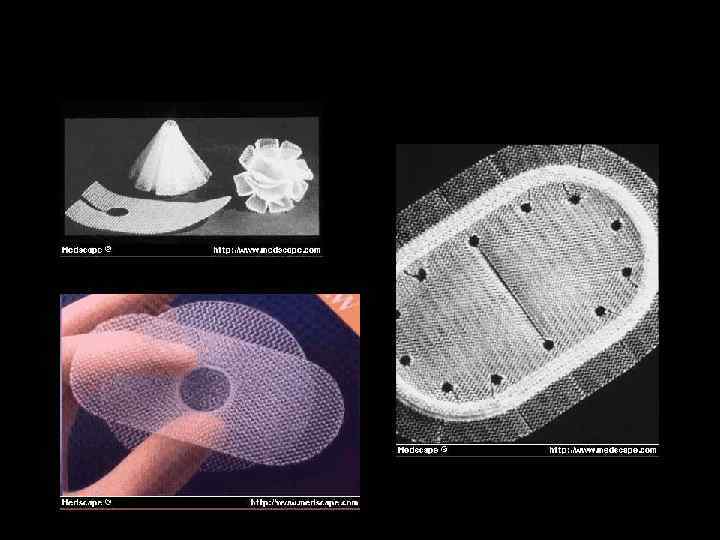

ПЛАСТИКА ГРЫЖЕВЫХ ВОРОТ • Местными тканями • Трансплантат "Секрет радикального грыжесечения будет найден лишь тогда, когда появится возможность производства искусственной ткани, столь же прочной, как фасции и сухожилия". Т. Биллрот, 1871 г.

ВАРИАНТЫ ФИКСАЦИИ ТРАНСПЛАНТАТОВ • sublay • inlay • onlay